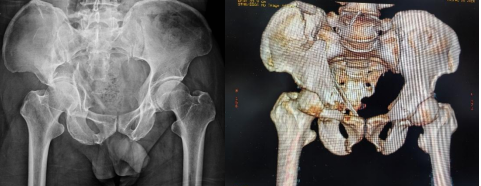

術前DR、CT重建片

患者林某,因高能量損傷導致髖臼骨折,骨折塊粉碎并移位,量大且復位固定操作異常艱難。傳統的內固定手術時間長、風險高,對于患者來說,不僅康復周期長,還可能面臨較高的并發癥風險。